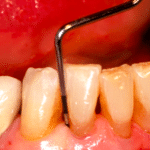

Ma come faranno questi batteri a creare infezione ed infiammazione?

Diversi sono i fattori di virulenza che vengono individuati in questi germi: da una tossina che danneggia le cellule dell’ospite e le difese immunitarie ad una inibizione della chemiotassi, alla presenza di enzimi che degradano il connettivo e riassorbono l’osso alveolare che circonda il dente… insomma una perfetta e sempre attiva macchina da guerra!

La stessa analisi microbiologica e virale è in grado di evidenziare anche la presenza di un fungo, la Candida Albicans.

Questo micete, che normalmente è un fungo opportunistico e che a volte può diffondersi nella bocca prendendo il nome di mughetto, può essere rilevato nelle tasche parodontali profonde aggravando la patologia parodontale.